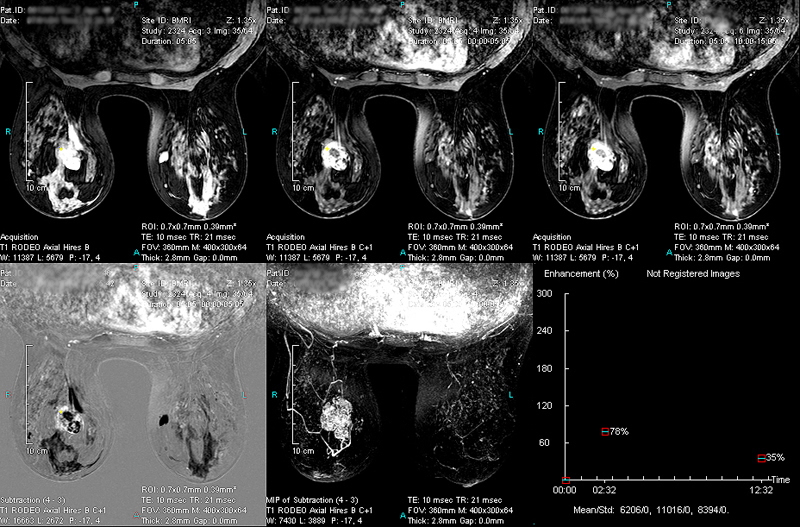

Case 2 - Over 4cm Infiltrating Ductal Carcinoma with Mucinous Component on right breast

(from left to right, top to down)

RODEO Pre (unspoiled), 1st Post (spoiled), 2nd Post (spoiled), Subtraction, MIP of Subtraction and TIC Curve